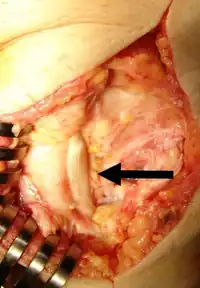

This condition may also be due to a para-articular/extraskeletal osteochondroma